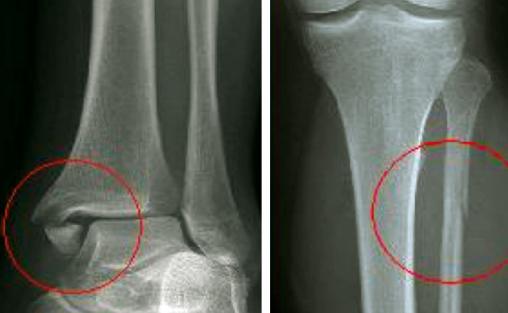

Fracture de Maisonneuve : fracture de la malléole médiale et du col de la fibula